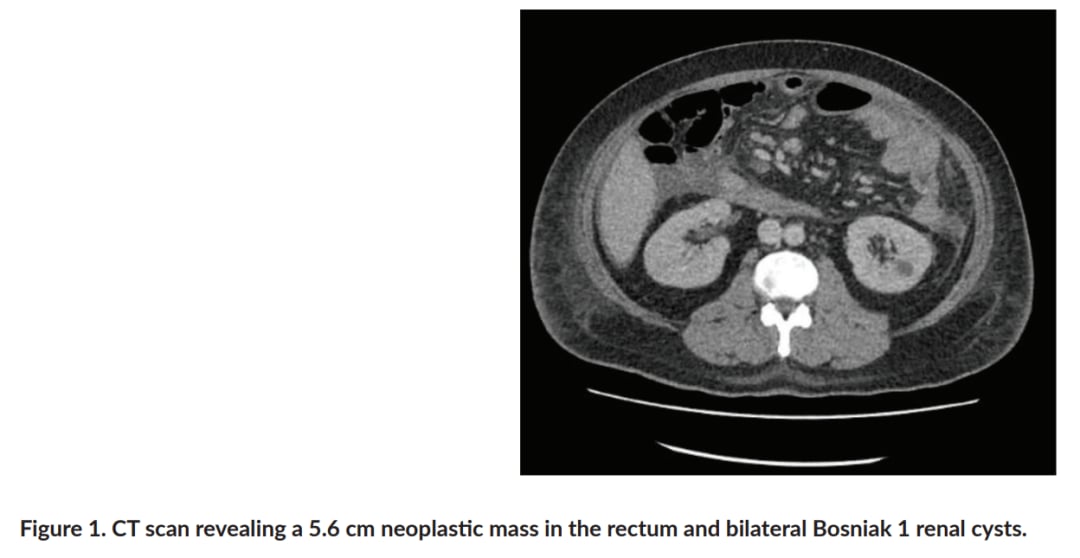

▲图1 CT扫描显示直肠内有一个 5.6 cm的肿瘤肿块和双侧Bosniak 1型肾囊肿

我们关注的这位35岁男性患者,其病程进展迅速,表现出多灶性肿瘤,包括直肠腺癌、结肠息肉病、非典型慢性髓系白血病和脑部肿块(提示髓母细胞瘤)。基因检测结果显示,他携带了CHEK2基因的胚系致病性变异、APC基因的一个新的胚系意义未明变异(VUS),以及JAK2 V617F体细胞突变。这些发现不仅解释了患者多发肿瘤的遗传基础,也强调了多基因相互作用在癌症发生发展中的关键角色。